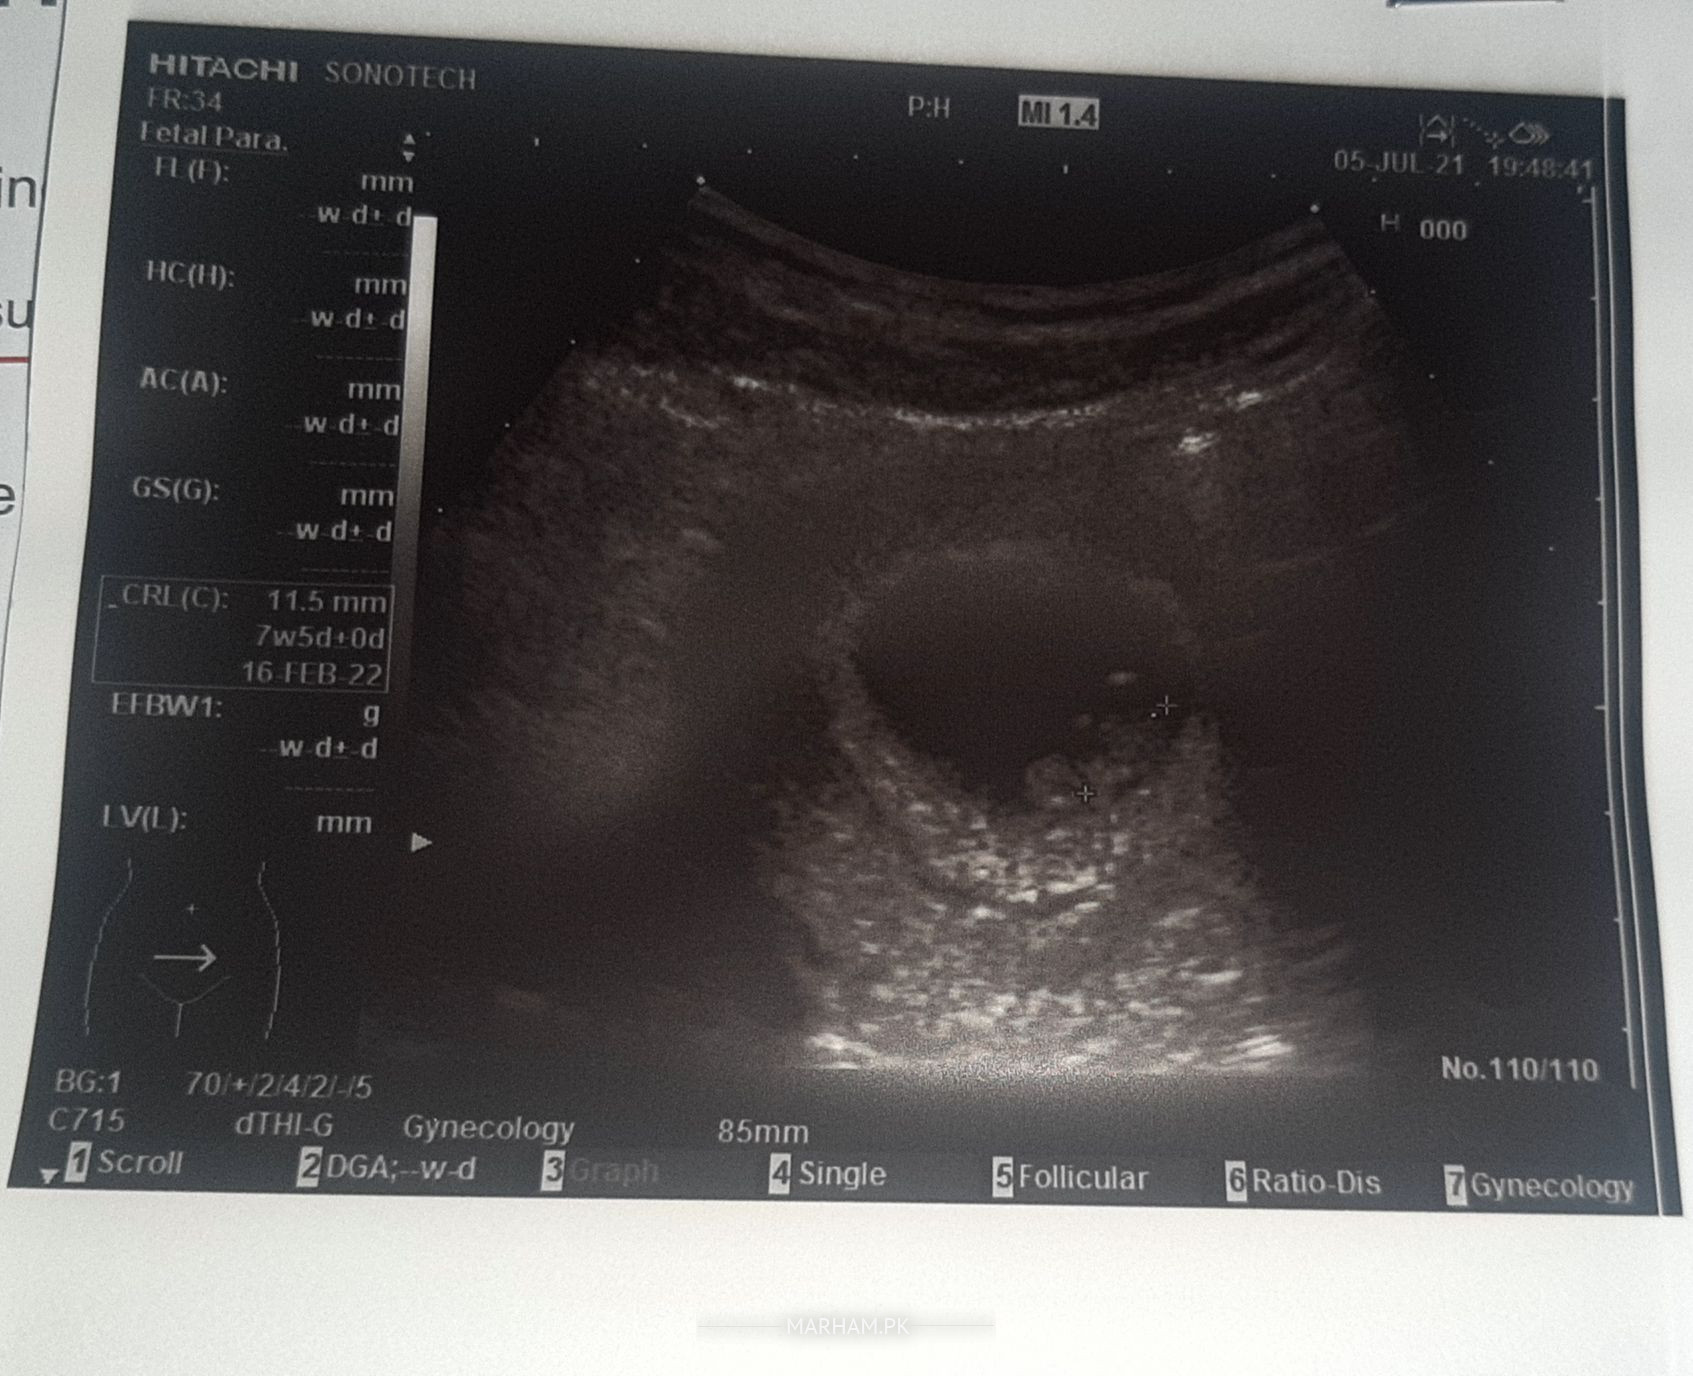

Asking For Self, Female 27, lahore

my reports are normal plz check my reports.

plz attach ultrasound report

report